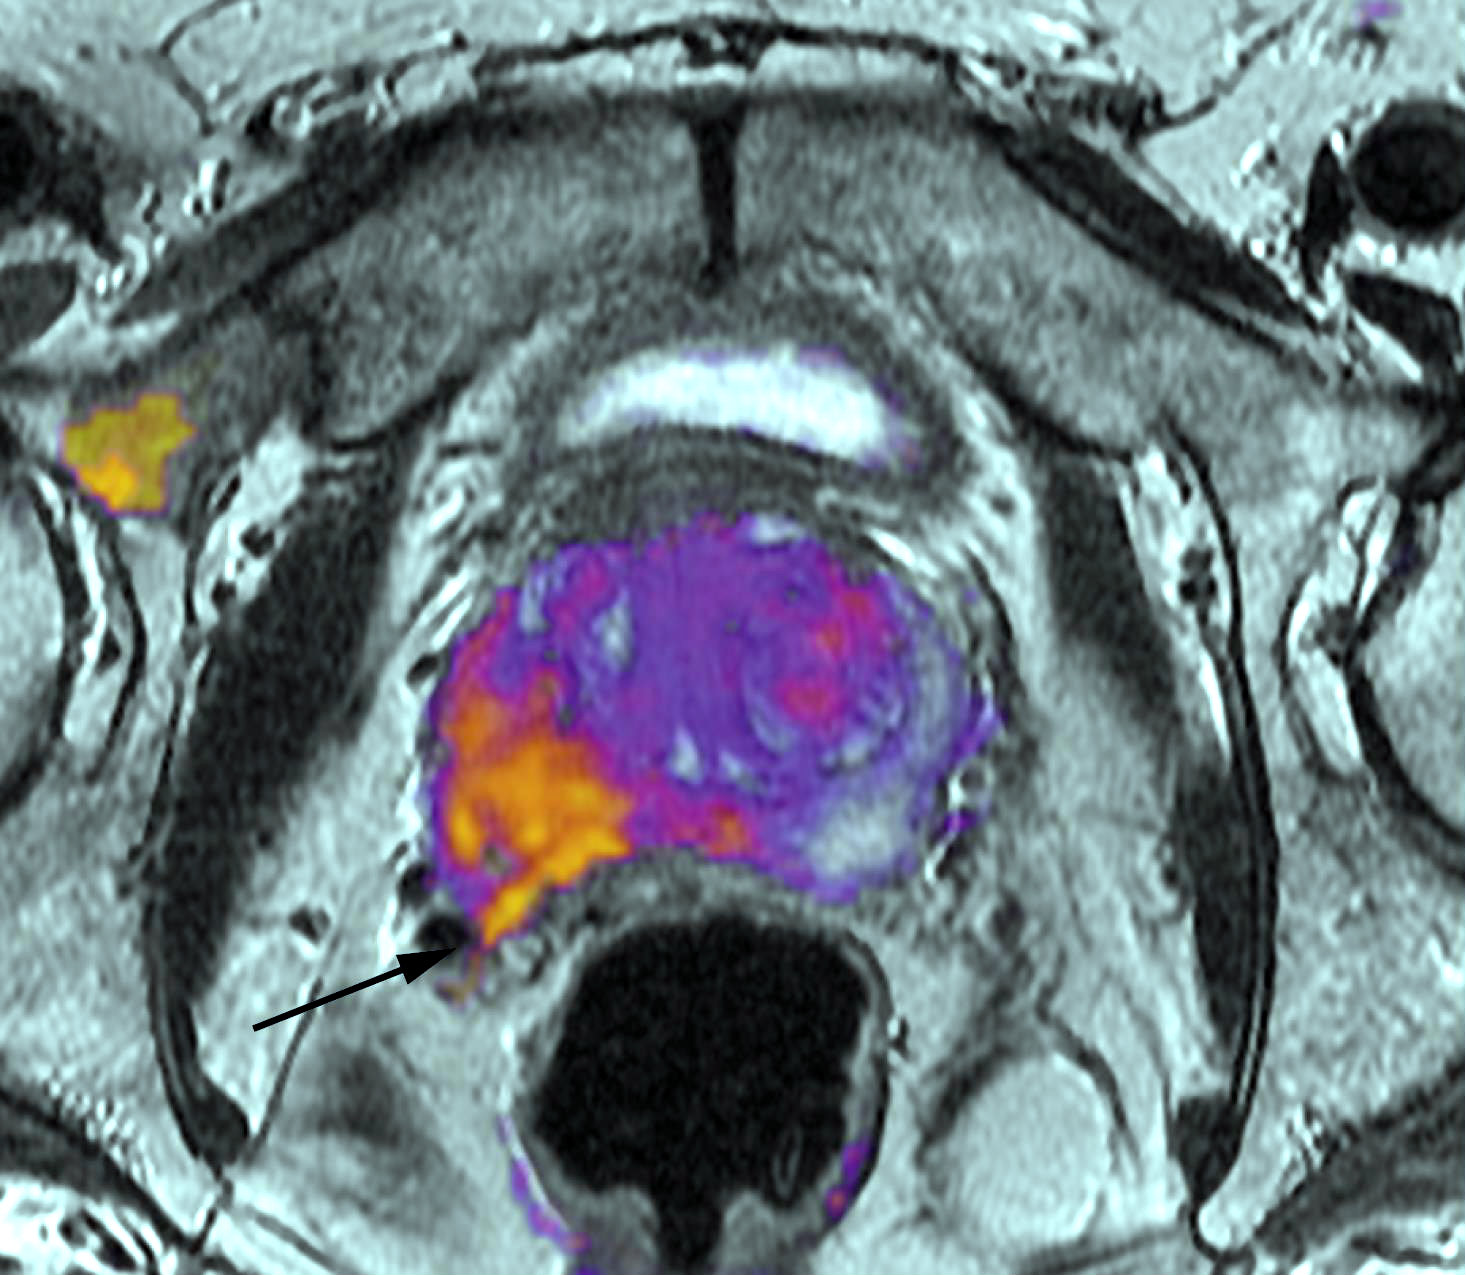

La presencia en plasma de ADN del virus Epstein-Barr tuvo una sensibilidad de 97,1% y una especificidad de 98,6% para el diagnóstico de carcinoma nasofaríngeo, realizado por endoscopía y resonancia magnética. New England Journal of Medicine, 10 de agosto de 2017